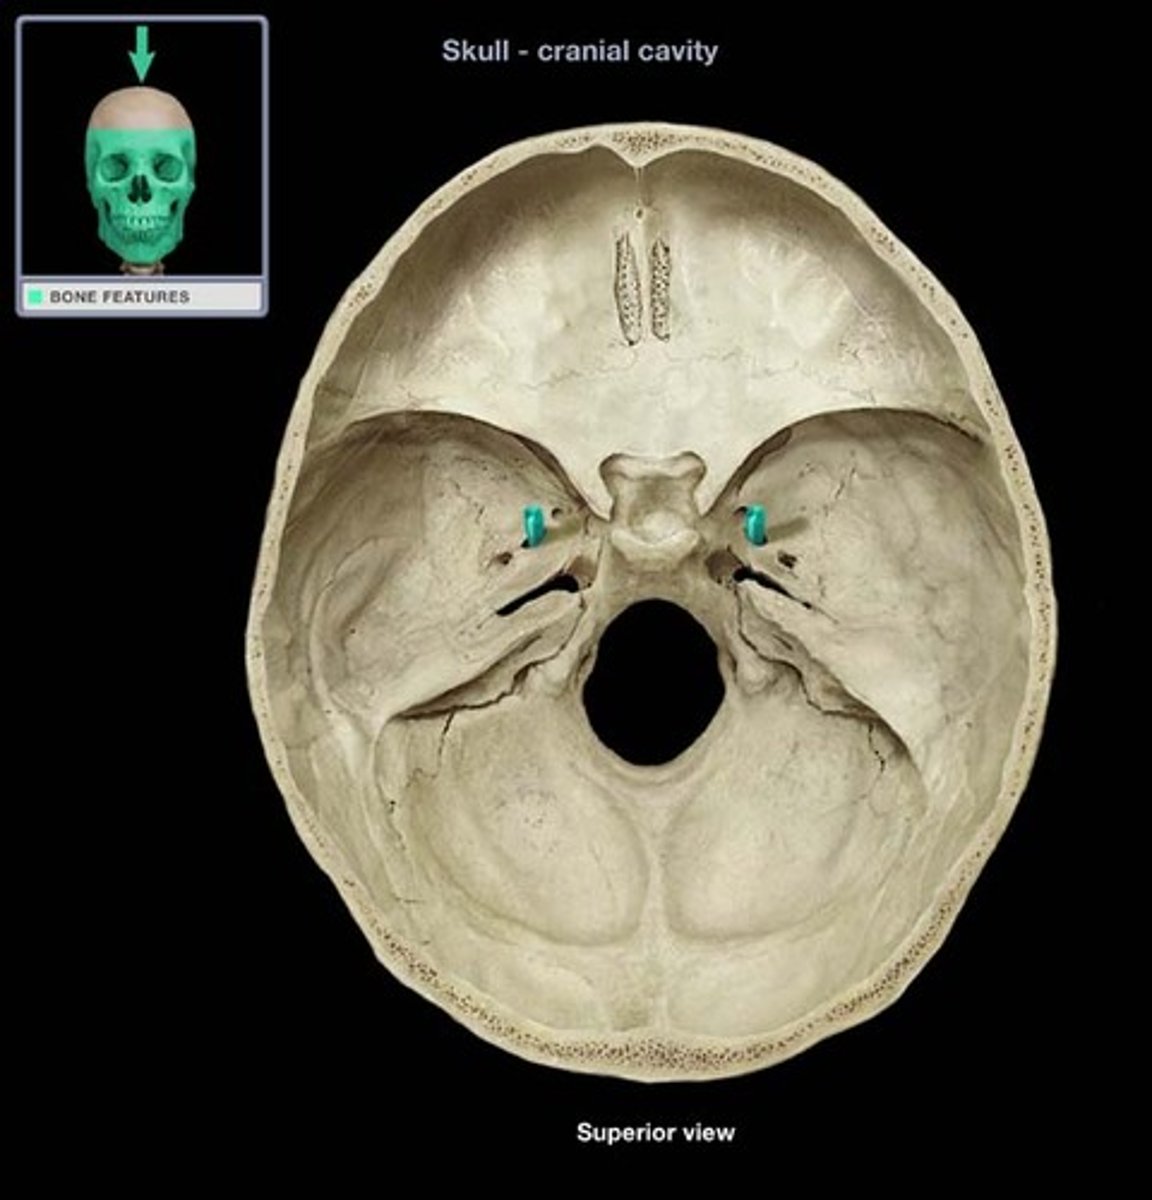

Foramen Ovale

An oval shaped opening in the middle cranial fossa located at the posterior base of the greater wing of the sphenoid bone. It transmits the mandibular division of the trigeminal nerve (CN V3) and the accessory meningeal artery.

Sella Turcica

Depression in the sphenoid bone where the pituitary gland is located

Internal Acoustic Meatus

A passage for CN VIII from the inner ear to the brain